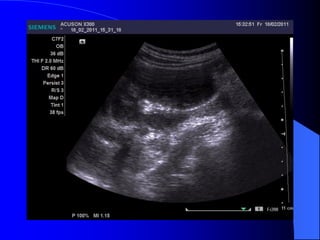

- Siãu ámphán biãût âæåüc khäúi âàûc vaì dëch. Nãúu laì khäúi âàûc seî xem xeït cáúu truïc ám, coï thãø giaím, âäöng hoàûc tàng ám, xem âäü âäöng nháút ám, väi hoïa. Nãúu laì khäúi dëch, seî tçm täø chæïc âàûc hoàûc vaïch trong nang. Siãu ám coï thãø tháúy haûch di càn, xám láún ténh maûch. Noïi chung khi phaït hiãûn khäúi âàûc trãn siãu ám, cáön chuûp CLVT âãø âaïnh giaï roî hån baín cháút, sæû xám láún, di càn.

- CLVT phánbiãût khäúi âàûc hay dëch, phaït hiãûn väi hoïa nhoí, xuáút huyãút trong u, tçnh traûng tæåïi maïu cuía u. Pháön låïn træåìng håüp phán biãût âæåüc u laình vaì u aïc. Xem xeït âæåìng dáùn niãûu bë giaîn, bë xám láún. CLVT kiãøm tra di càn haûch xám láún vuìng xung quanh, xám láún maûch maïu, di càn xa, cå såí âãø phán giai âoaûn tiãún triãøn u, cáön thiãút cho phæång phaïp âiãöu trë.